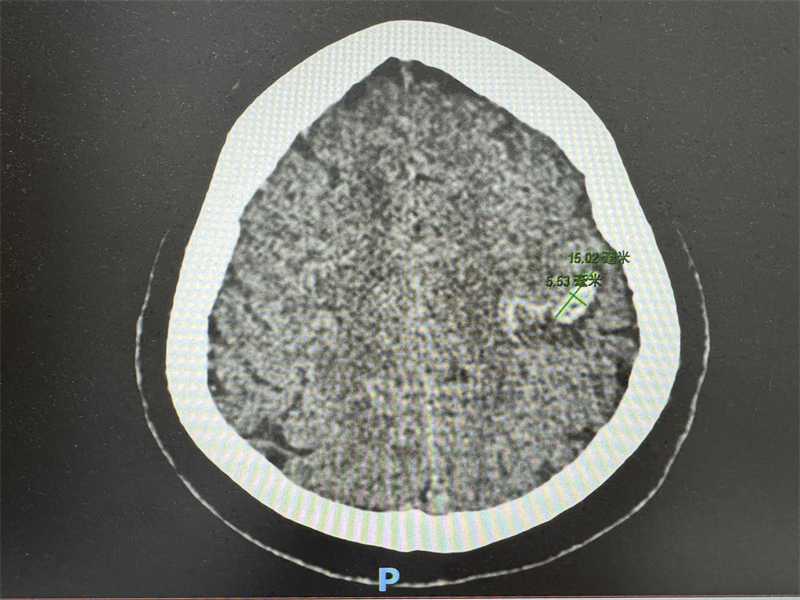

事件的緊迫性始于一次常規的健康體檢。當天上午,柳州市人民醫院健康管理中心的醫務人員接到放射科發出的危急值報告:一位今早來院體檢的人員,其頭顱CT檢查結果提示左側額葉新發腦出血伴少量蛛網膜下腔出血。這一結果意味著該體檢者顱內正在出血,病情極其兇險,隨時可能發生猝死,生命危在旦夕。